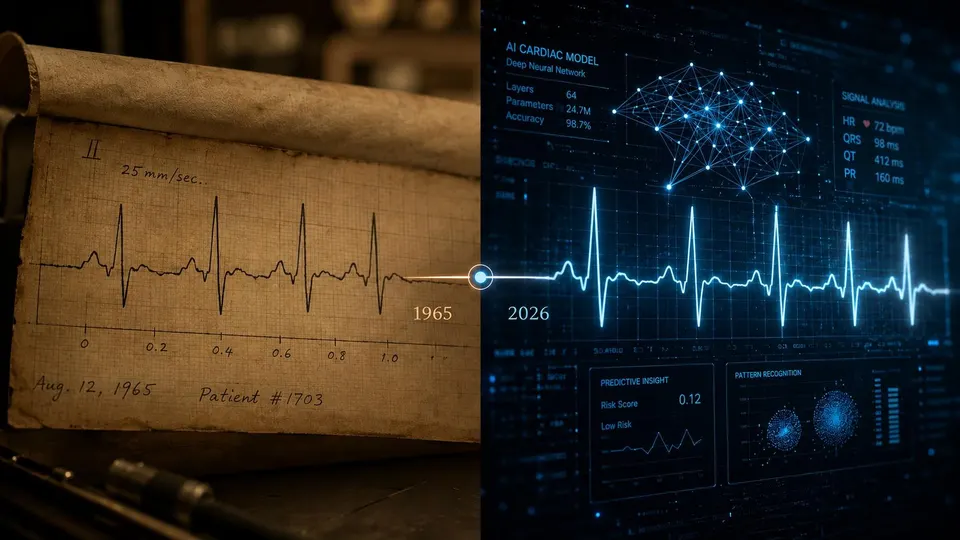

Illustration by Anumana // Why bring AI into a test that has been around for a hundred years? | Each of my stories includes an original artwork. Clicking on them will take you to their websites. I am grateful for all the collaborators, sharing…